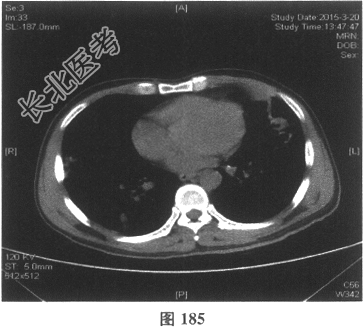

- [材料题] 患者男性,52岁,因间断发热伴咳嗽,咳少许黄痰,无咯血,伴胸闷憋气20余天就诊。体检:体温37.6~38.3℃。既往体健。查体:体温37.6℃,心率83次/分,呼吸20次/分,血压117/64mmHg。神志清,精神可,口唇无发绀;双肺呼吸音粗,可闻及广泛干、湿性啰音,以干啰音为主;心率83次/分,律齐,各瓣膜听诊区未闻及病理性杂音;腹软,无压痛及反跳痛,肠鸣音3次/分,双下肢无水肿。血常规检查:白细胞计数26.32×109/L,中性粒细胞0.846,血红蛋白117g/L,血小板计数1911×109/L;C反应蛋白119.05mg/L。尿常规检查:隐血2(+),蛋白1(+)。痰培养:曲霉菌属,请排除污染。生化全套检查:白蛋白19.6g/L,谷丙转氨酶24.2U/L,谷草转氨酶25.8U/L,γ-谷氨酰基转移酶91.4U/L;尿素氮13.00mmol/L(2.14~7.14mmol/L),肌酐166.8μmol/L(31~132μmol/L);血钾5.6mmol/L。肺部CT见图178~图185。

- 多项选择题4.[提示]患者应用多种抗生素治疗(第三代头孢菌素、青霉素加酶抑制剂)包括抗曲霉菌治疗无效,加用甲泼尼龙40mg静脉滴注病情好转。肺部CT检查显示病变明显改善。尿常规检查正常, 肾功能检测正常。复查肺部CT(图188~图195):示病变较前好转。Wegener肉芽肿的主要临床表现是( )